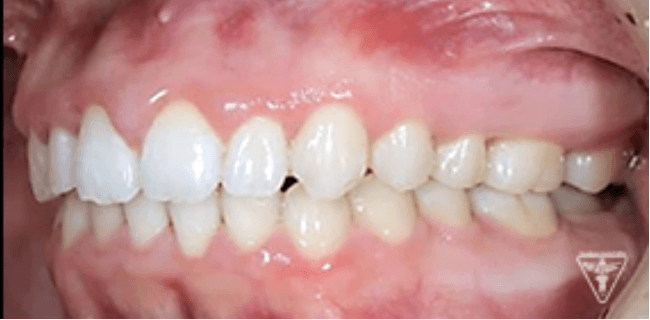

治療前後の比較

治療後